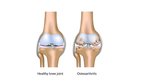

Osteoartrīts, arī osteoartroze ir locītavu slimības veids. Izraisa locītavu virsmu skrimšļu nodilumu un sekojošus bojājumus

Biežākie simptomi ir locītavu sāpes un stīvums. Sākumā tie var parādīties pēc fiziskām aktivitātēm, tomēr ar laiku simptomi var būt pastāvīgi. Vēl var būt locītavu pietūkums, ierobežota kustības spēja; gadījumos, kad tiek ietekmēta mugura, var būt roku un kāju vājums vai nejutīgums. Visbiežāk slimība skar pirkstu galu, īkšķa pamatnes, kakla, muguras, ceļgalu un gurnu

locītavas. Biežāk tiek skartas locītavas vienā ķermeņa pusē, nekā tās pašas otrā pusē. Problēmas parasti rodas gadu gaitā. Atšķirībā no citu veidu artrītiem, osteoartrīts parasti skar vienīgi locītavas.…